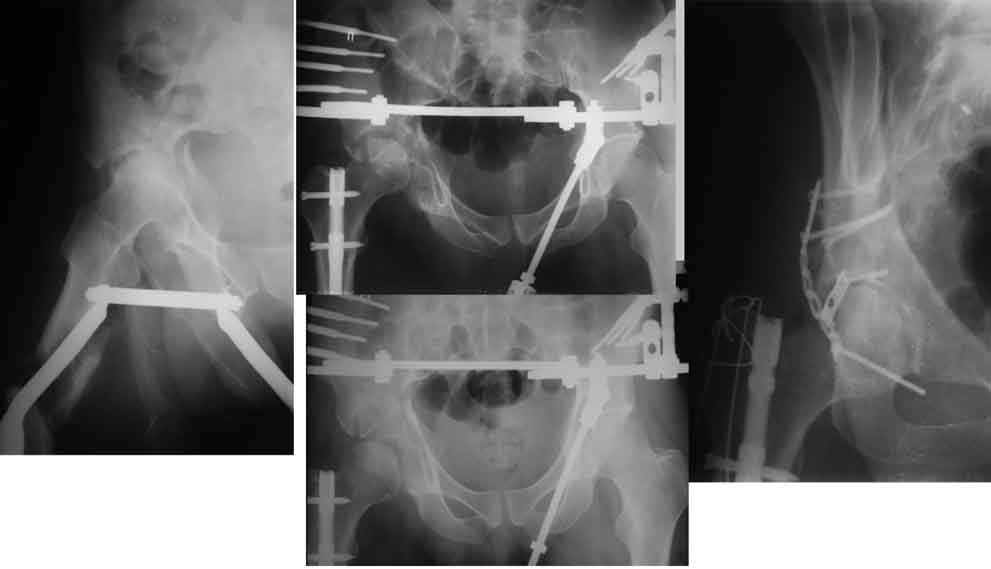

Изначально я бы при поступлении наложил аппарат таз+оба бедра, с

фиксацией вертельной области.

Затем при выходе из кризиса и заживления раны на колене ЗИМО ретроградно

+ Yобразный доступ с синтезом вертлуги.

если надо коррегировать - ЧКО с этой стороны, затем ретроградно гвоздь с

рассверливанием проксимального канала.

Пример с антеградным введением стержня (застарелый случай)

У тебя тоже можно воспользоваться этой методой, однако настоятельно

рекомендую ЗИМО делать в аппарате (дистракционном устройстве) и лишь

потом открыто вертлугу.